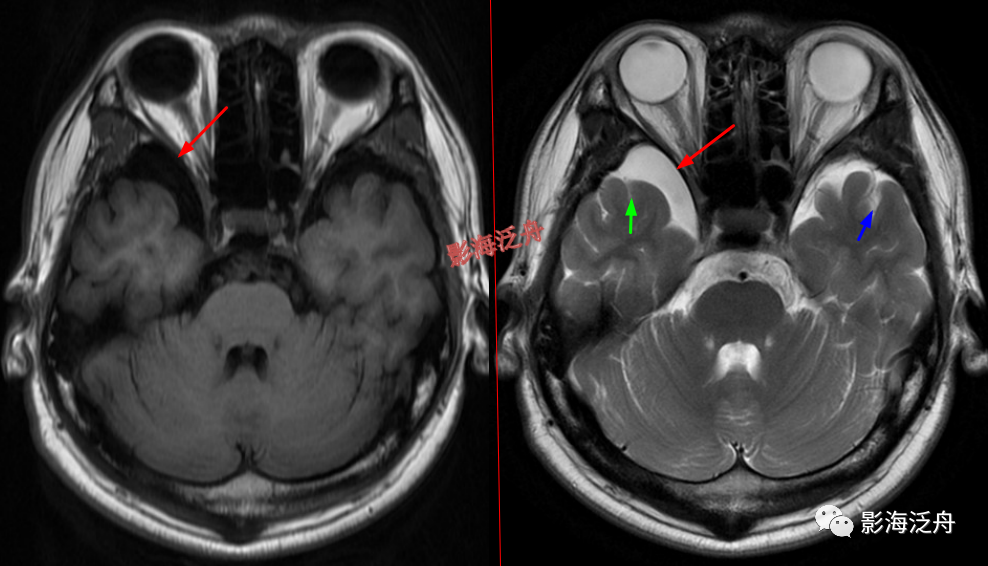

延髓左侧小梗死灶。这种斑点状的梗死灶漏诊也非常多见,患者症状一般不明显,我自己漏诊过两次。小的梗死灶多见于脑干、侧脑室周围,大脑皮层区一般不多见。因此,重点区域进行细致观察,可以减少此类疾病的漏诊。

颞极前方蛛网膜囊肿(红箭)漏诊率也比较高,尤其在老年患者中,常常被误认为是扩大的蛛网膜下间隙,仔细观察可以发现右侧颞叶受压,脑沟闭塞(绿箭),与健侧(蓝箭)对比更为明显。